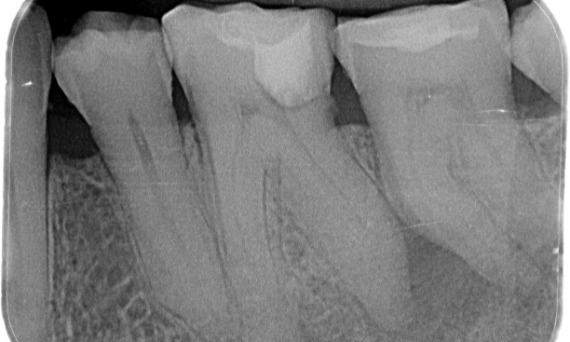

Önce: Muayenede, sağ alt ilk molar ile ilişkili çürük lezyonu mevcuttu. Radyografik incelemede lezyonun pulpa boynuzuna yakınlığı görüldü ve temel şikayet ile birleştirilince kronik geri dönüşümsüz pulpitis tanısı konuldu.

Sonra: Erişim kavitesi mümkün olduğunca konservatif olarak yapıldı. TruNatomy, genç hastanın yaşı nedeniyle tercih edilen sistem oldu. Dişin oklüzal yükün üstesinden gelme yeteneğini artırmak ve son restorasyonun ömrünü uzatmak amacıyla dentini mümkün olduğunca korumamız gerekiyordu.